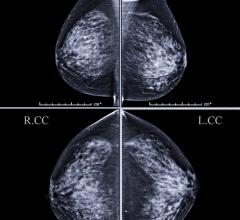

May 19, 2020 — Women with mammographically detected breast lesions that are probably benign should have follow-up ...